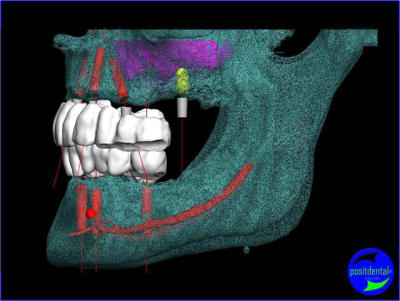

Tu trouve l’emplacement de l’implant en 26 « cocasse », sa position n’est pas choisie par hasard mais correspond au renforcement de la voute sinusienne.

projet implantaire pour février

1er étape le wax-Up, dans ce cas clinique il est réalisé en 3D

un autre exemple d'extraction implantation au maxillaire